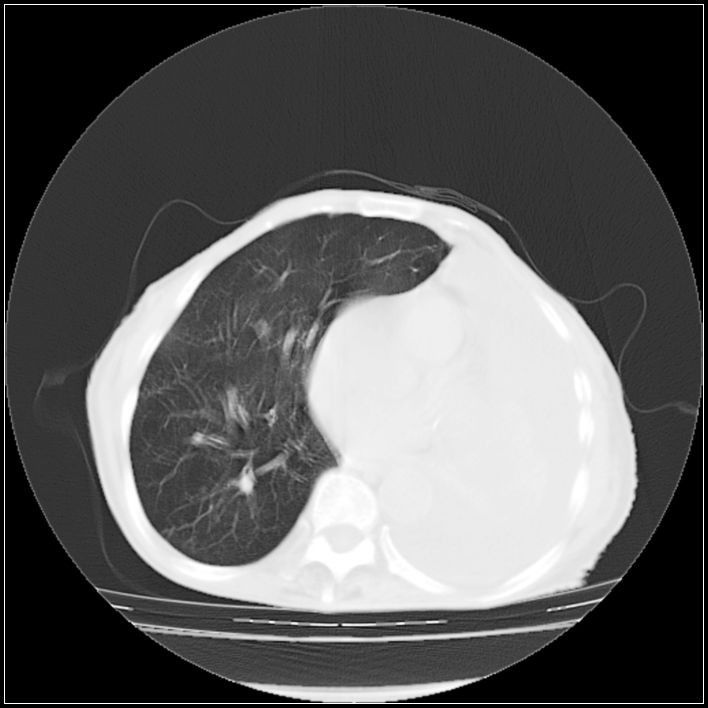

以下是引用ydx_74在2008-5-31 16:08:00的发言:[br]中心性肺癌并左侧肺不张、胸水。

以下是引用影象小辈在2008-5-31 16:25:00的发言:[br]左侧胸腔团状不规则致密影,界欠规整,密度不均匀,其内可见更低密度影及高密度影,并可见包裹性胸腔积液 考虑为1.畸胎瘤 2.肺癌